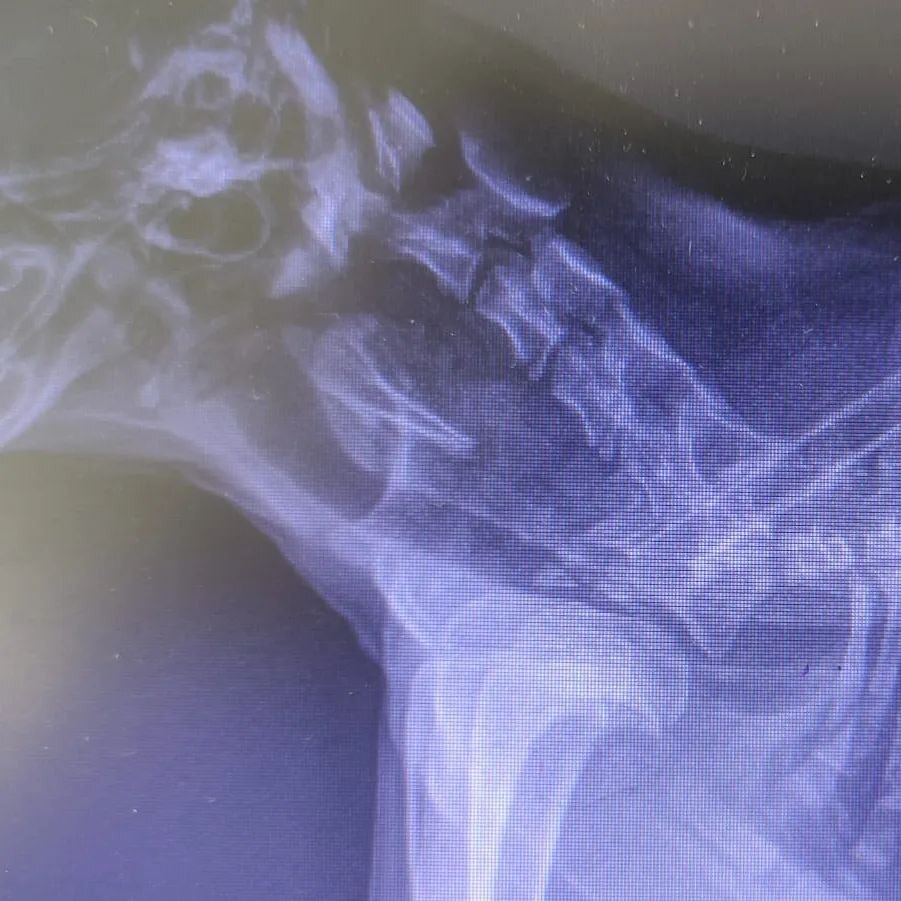

А это Мишка, его нашли умирающим на улице

Малыш проглотил кость, которая застряла в горле и причиняла страдания щеночку.

В клинике Мишке помогли, смогли достать косточку без операции. Подлечившись в стационаре, ребёнок приехал к нам, пока в домашний стационар, на долечивание и восстановление.